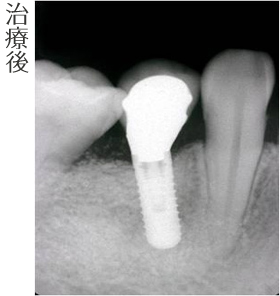

両隣りの歯を削らずにインプラント治療を行いました。

- インプラント(1本)

- ソケットプリザベーション

- インプラント上部セラミック冠 (1本)